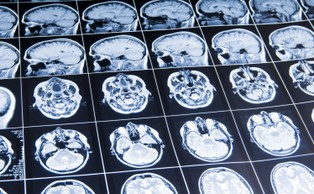

leki steroidowe

Leki steroidowe mogą powodować zmiany w strukturze mózgu [BADANIA]